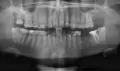

Здравствуйте. От 6-го нижнего зуба остался один корень. Зуб не болит, нервы удалены, каналы запломбированы. Зуб нужно удалить. Насколько сложна данная процедура и будут ли мне резать десну? Спасибо.

Добрый день! Если разрушение зуба не ниже основания десны и при этом каналы хорошо (!!!) пролечены (нет воспалительных процессов, грануляций), и ткани зуба плотные, то зуб можно восстановить культевой восстановительной вкладкой, а затем коронкой. Я вам рекомендую обратиться на прием к грамотному ортопеду для анализа состояния корня зуба. Если потребуется моя помощь , обращайтесь всегда рад вам помочь.